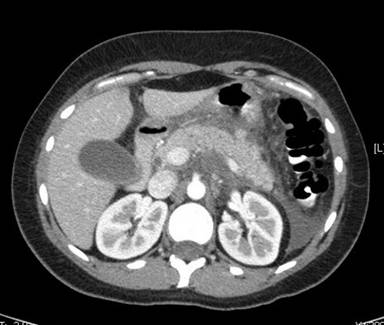

An ultrasound of the right upper quadrant was unremarkable, without evidence of cholelithiasis. Abdominal computed tomography (CT) scan revealed significant inflammatory changes including peripancreatic fluid and fat stranding that extended into the pericolic gutter as well as thickening of the posterior gastric wall, left perinephric stranding, and periportal edema with normal pancreatic anatomy. Magnetic resonance cholangiopancreatography (MRCP) performed two days after admission revealed similar peri-pancreatic inflammatory changes and normal pancreatic anatomy. There was no evidence of gallstone or sphincter dysfunction. The changes discussed above are represented in Figures 1, 2, and 3.

Figure 1. Extensive peripancreatic inflammatory changes and stranding is evident on the CT image shown here. Fluid is seen in the pericolic gutter and surrounding the liver. |